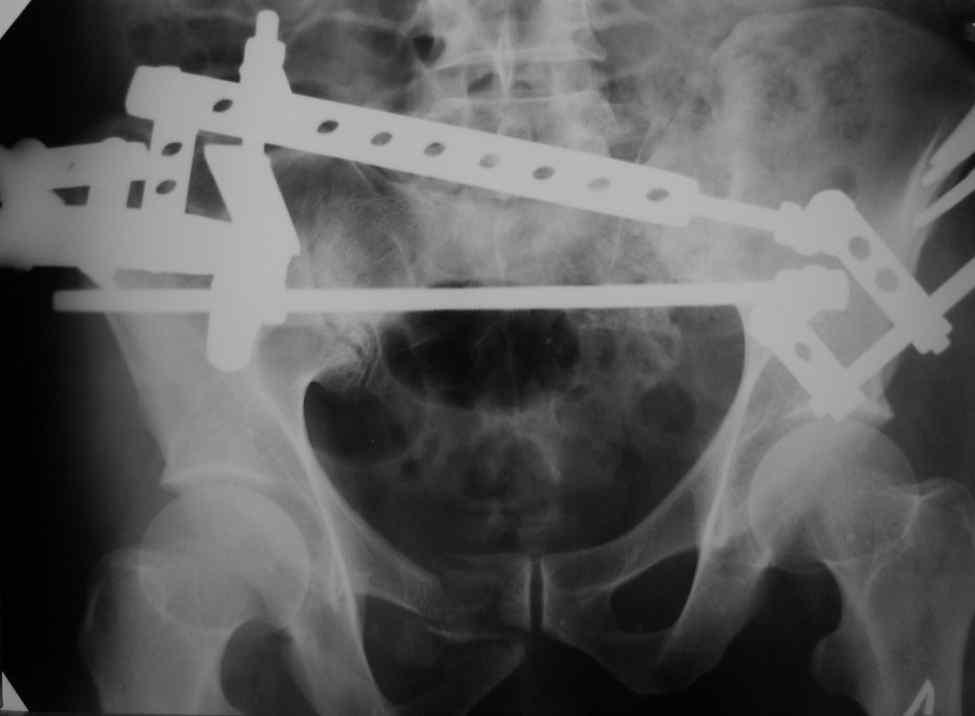

Можно посмотреть на нынешние снимки таза в аппарате, фас и inlet?

Отправитель: Владимир Бахарев 16 Ноябрь 2006, 12:13

Снимки вот

> (перелом лонной, седалищной костей справа . Разрыв КПС слева)

может быть и двустороннее повреждение задних отделов

> извинямси за качество R-грамм).

> Сохроняется смещение. Попытаемся его устранить этапно, но сомневаемся,

> хватит ли жесткости АВФ, и нет нигде методики введения илиосакральных

> винтов! Подскажите другие варианты!

по представленным рентгенограммам понять почти ничего невозможно из-за низкого качества, снимки идут в динамике? Для уточнения характера повреждения таза необходимо сделать хотя бы "inlet". повреждение представляется вертикально-нестабильным, в этом случае устранить краниальное и, возможно, передне-заднее смещение "передней рамой" невозможно и дело тут не в жесткости АВФ. Кольцевой опорой можно сделать все что угодно.

А методика проведения илиосакральных винтов есть и в Мюллере, на odoc.ru тоже доступно (правда там обсуждается транссакральная фиксация, но принципы те же). Единственно, методика введения винтов в классическом варианте предполагает положение пациента на животе, что в условиях аппарата затруднительно, поэтому мы делаем на спине, используя спицы в качестве ориентиров, кроме того лучше использовать канюлированные (проще).